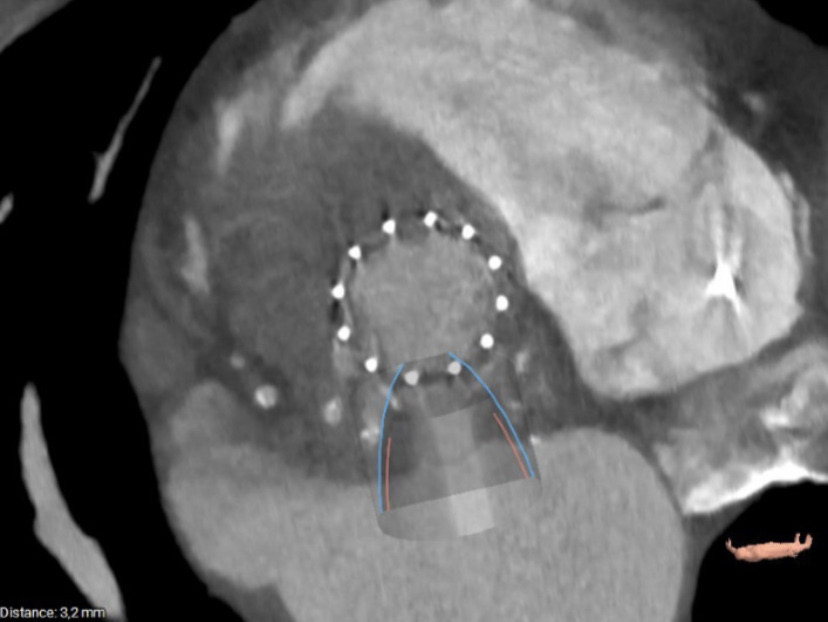

BACKGROUND Transcatheter mitral valve-in-valve implantation (TMVIV) into failing surgical bioprosthetic valves has evolved in recent years as a promising therapy to avoid redo cardiac surgery in patients at high surgical risk. METHODS An 80-year-old female patient with CKD stage 3, hypertension, a permanent PMK and atrial fibrillation was referred to our institution with NYHA Class III symptoms. She has undergone implantation of a bioprosthetic valve (St Jude Epic 29 mm) for severe mitral insufficiency due to chordal rupture in 2017 and transcatheter aortic valve implantation (Edwards 29 mm) for severe aortic insufficiency in 2022. The patient presented with structural valve degeneration, defined as intrinsic permanent variations of the tissue components of the valve, culminating in the development of severe intra-prosthetic stenosis. Notably her echocardiogram showed LVEF 45% with severe mitral valve deterioration due to calcification (mean gradient 15 mmHg, 3D MVA 0.8 cm^2). TAVI was normally functioning. Surgical risk for redo procedure was too high after evaluation by our Heart Team (EuroScore II 23,6%, STS Score operative mortality 16,7%). So, we have decided for a TMVIV using Edwards SAPIEN 3 Resilia valve 29 mm, implanted reversely in mitral position. The pre-procedural assessment for the "sizing" of the valve was performed using computed tomography angiography (CT). The following parameters were evaluated: the mitral annulus area, the aorto-mitral angle, the inverse angle and the distance between the two valves for evaluation of the neo-LVOT. The area of the mitral annulus was 6.2 cm² and thus suitable for a Sapien 3-29 mm. During procedure, angiographic imaging, but no TEE, suggested for a likely interference between the mitral valve balloon and the aortic frame, so we prepared for a simultaneous kissing balloon inflation between the mitral and aortic valves. RESULTS The post-procedural TEE showed no gradient, no obstruction in LVOT and no leak for either valves. CONCLUSIONS To our knowledge, we present a rare case of successful treatment utilizing simultaneous kissing balloon inflation during mitral valve replacement due to bioprosthesis degeneration, employing the Edwards SAPIEN 3 Ultra RESILIA valve. The case was characterized by challenges in visualizing the bioprosthetic valve ring as a reference point due to calcification.